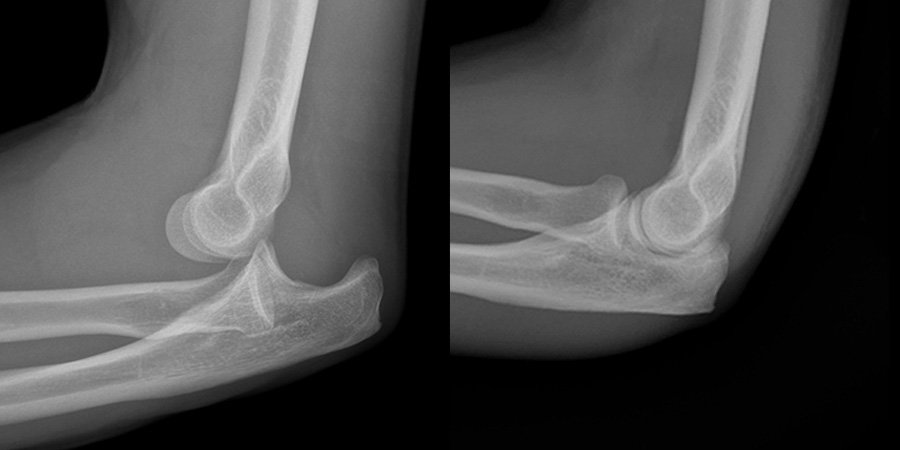

Elbow Dislocation

Clinical features of elbow dislocation:

3. Deformity.